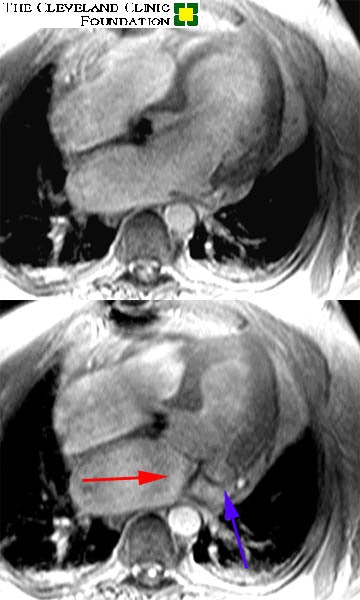

Image set #1 is a two chamber long axis view through the left ventricle and left atrium. Image set #2 is a four chamber view. The upper images are in diastole, while the lower are in systole. The red arrow demonstrates the turbulent jet of regurgitant blood flowing back into the left atrium. Regurgitation has occurred as a result of the 'prolapsing' posterior leaflet of the mitral valve noted by the blue arrow.

Image 2: